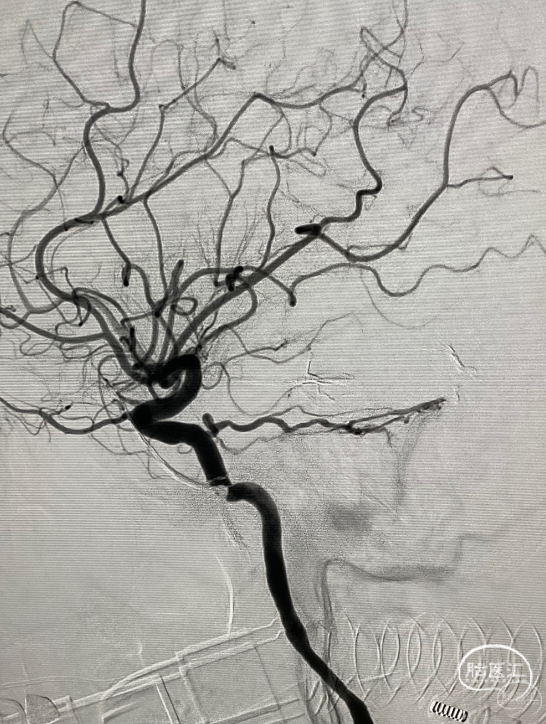

第五台是小脑动静脉畸形。

Glubran胶栓塞。

栓塞后畸形基本不显影。